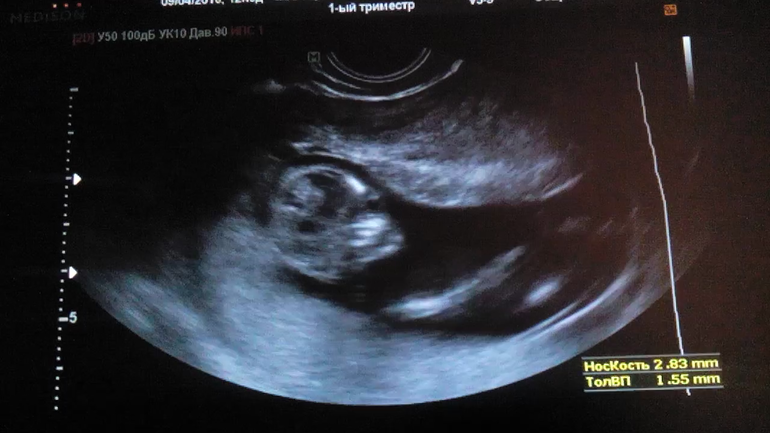

Сходила на первый скрининг в 1 советскую, точнее не сходила, а муж свозил, пришла самая первая, вся испереживалась, в конечном счёте сделали УЗИ и я увидела, своего малышастика впервые за всё это время, записала на видео в телефон, чтобы мужу показать) по результатам всё хорошо, счастье пришло на смену переживанию. Потом мы поехали выбирать холодильник, взяли фирму бошь и в подарок блендер, я как раз хотела для будущего приобретать, а тут подарок, приятненько ))) и чайник тефаль на газу,чтобы греть. Вообще получился настоящий день семьи, в день семьи, любви и верности )